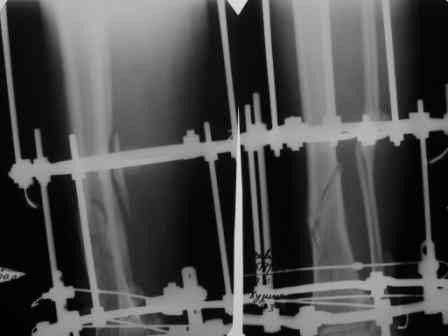

Уважаемые коллеги, пердлагаю к обсуждению больную 50л. Оперирована 4 июня 2006г авф.

На сегодня - состояние консолидации представлено на рентгенограммах. Имеется ли целесообразность реостеосинтеза интрамедуллярным гвоздем? Все зависит от пожелания больной? Чего хочет больная пока не спрашивал, поскольку никто в отделении не согласился

даже с относительным показанием к интрамедулярному реостеосинтезу. Нужна ли коррекция оси б/берцовой кости? Хотелось бы услышать ваше мнение. Спасибо.